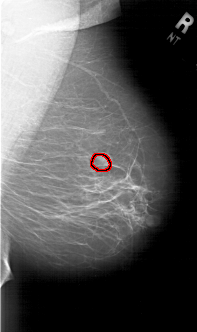

FILE: A_1765_1.RIGHT_CC.OVERLAY

TOTAL_ABNORMALITIES 1

ABNORMALITY 1

LESION_TYPE MASS SHAPE OVAL MARGINS OBSCURED

ASSESSMENT 4

SUBTLETY 4

PATHOLOGY BENIGN

TOTAL_OUTLINES 1

BOUNDARY